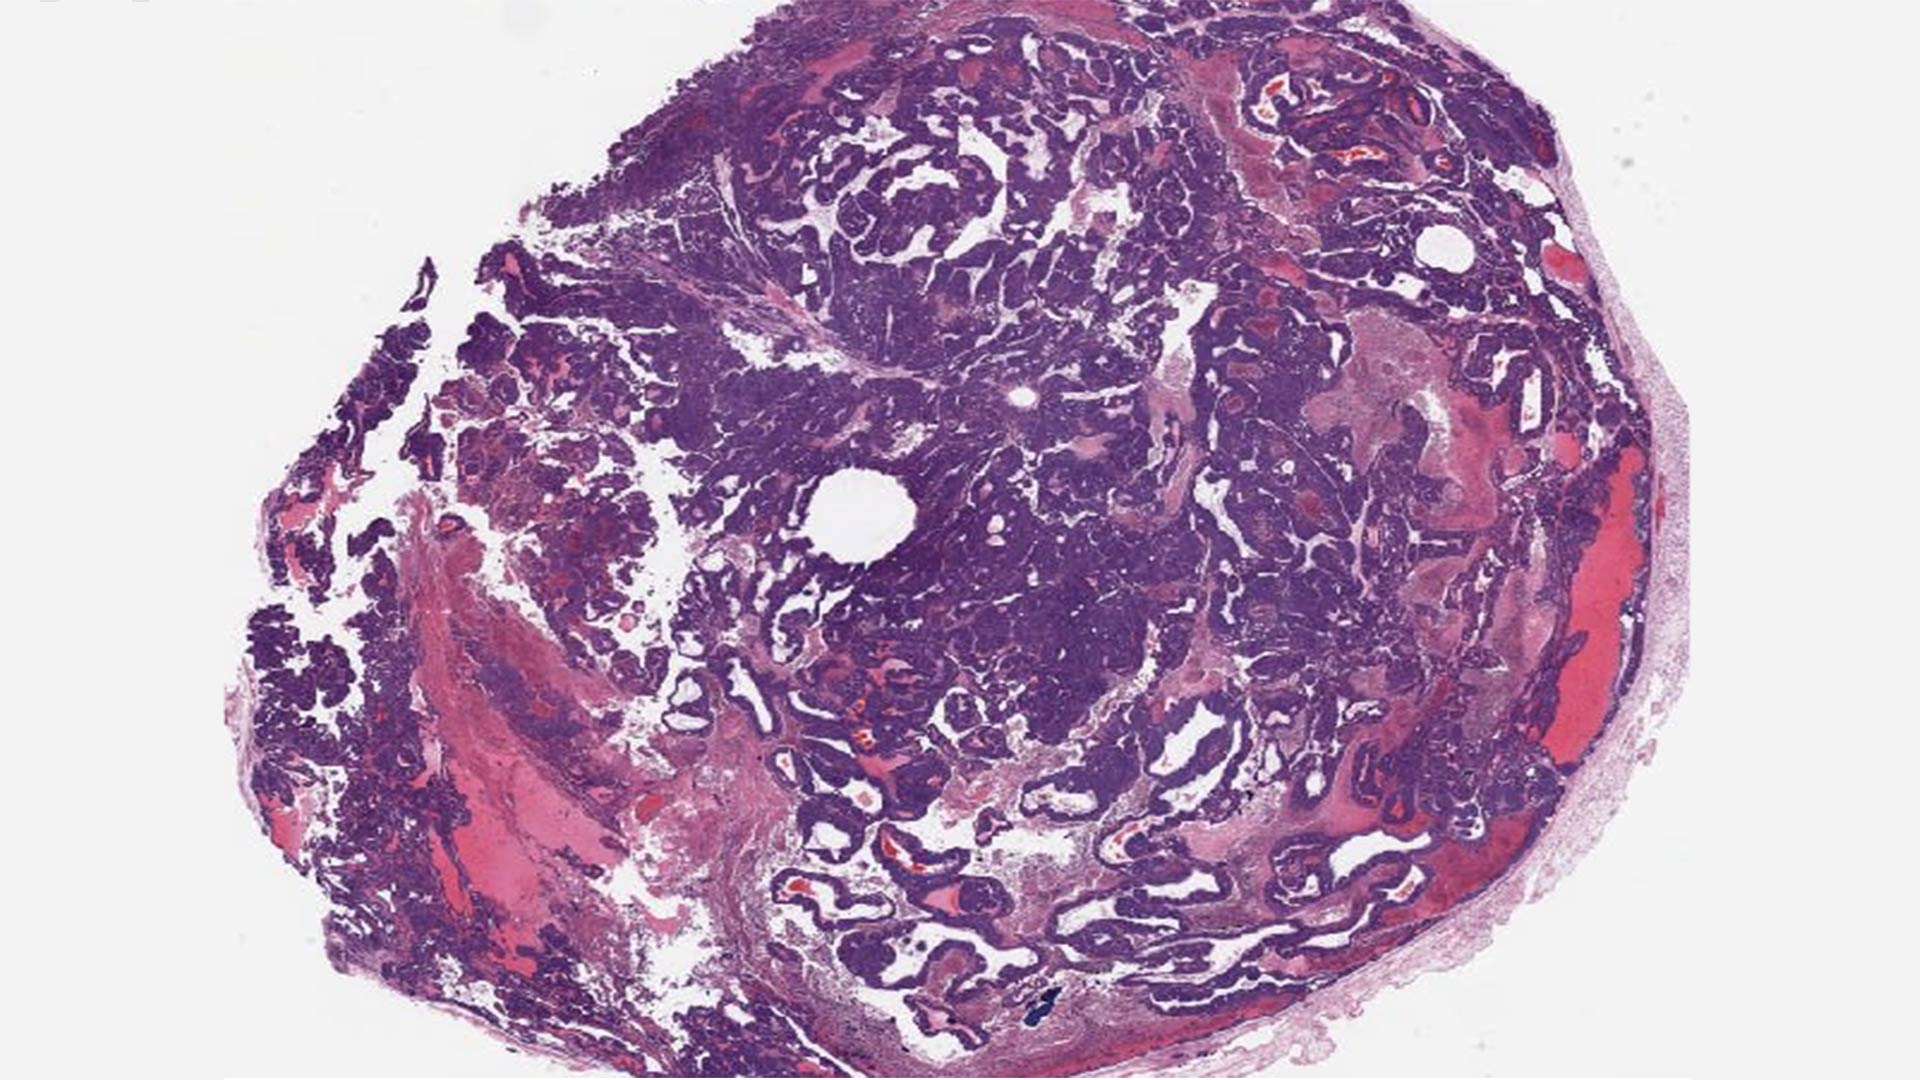

Previous research had found that knocking out BPTF slows breast cancer growth but doesn’t stop tumors from forming. As such, pharmaceutical companies didn’t see much promise in the protein. However, Ciccone and his lab-mates, graduate student Dhivyaa Anandan and postdoc Deeptiman Chatterjee, saw untapped potential. To learn more, they bred a classic breast cancer mouse model with a BPTF knockout mouse. To their surprise, they found the tumors in the crossbred mice remained ER+ throughout their development.

“There isn’t any mouse model that maintains a hormone-positive cancer throughout the cycle of the tumor,” Ciccone said. When treated with tamoxifen, one of the most common hormone therapies for ER+ breast cancer, the tumors were “responding and not growing,” he said. “That’s when we realized that we were onto something.”